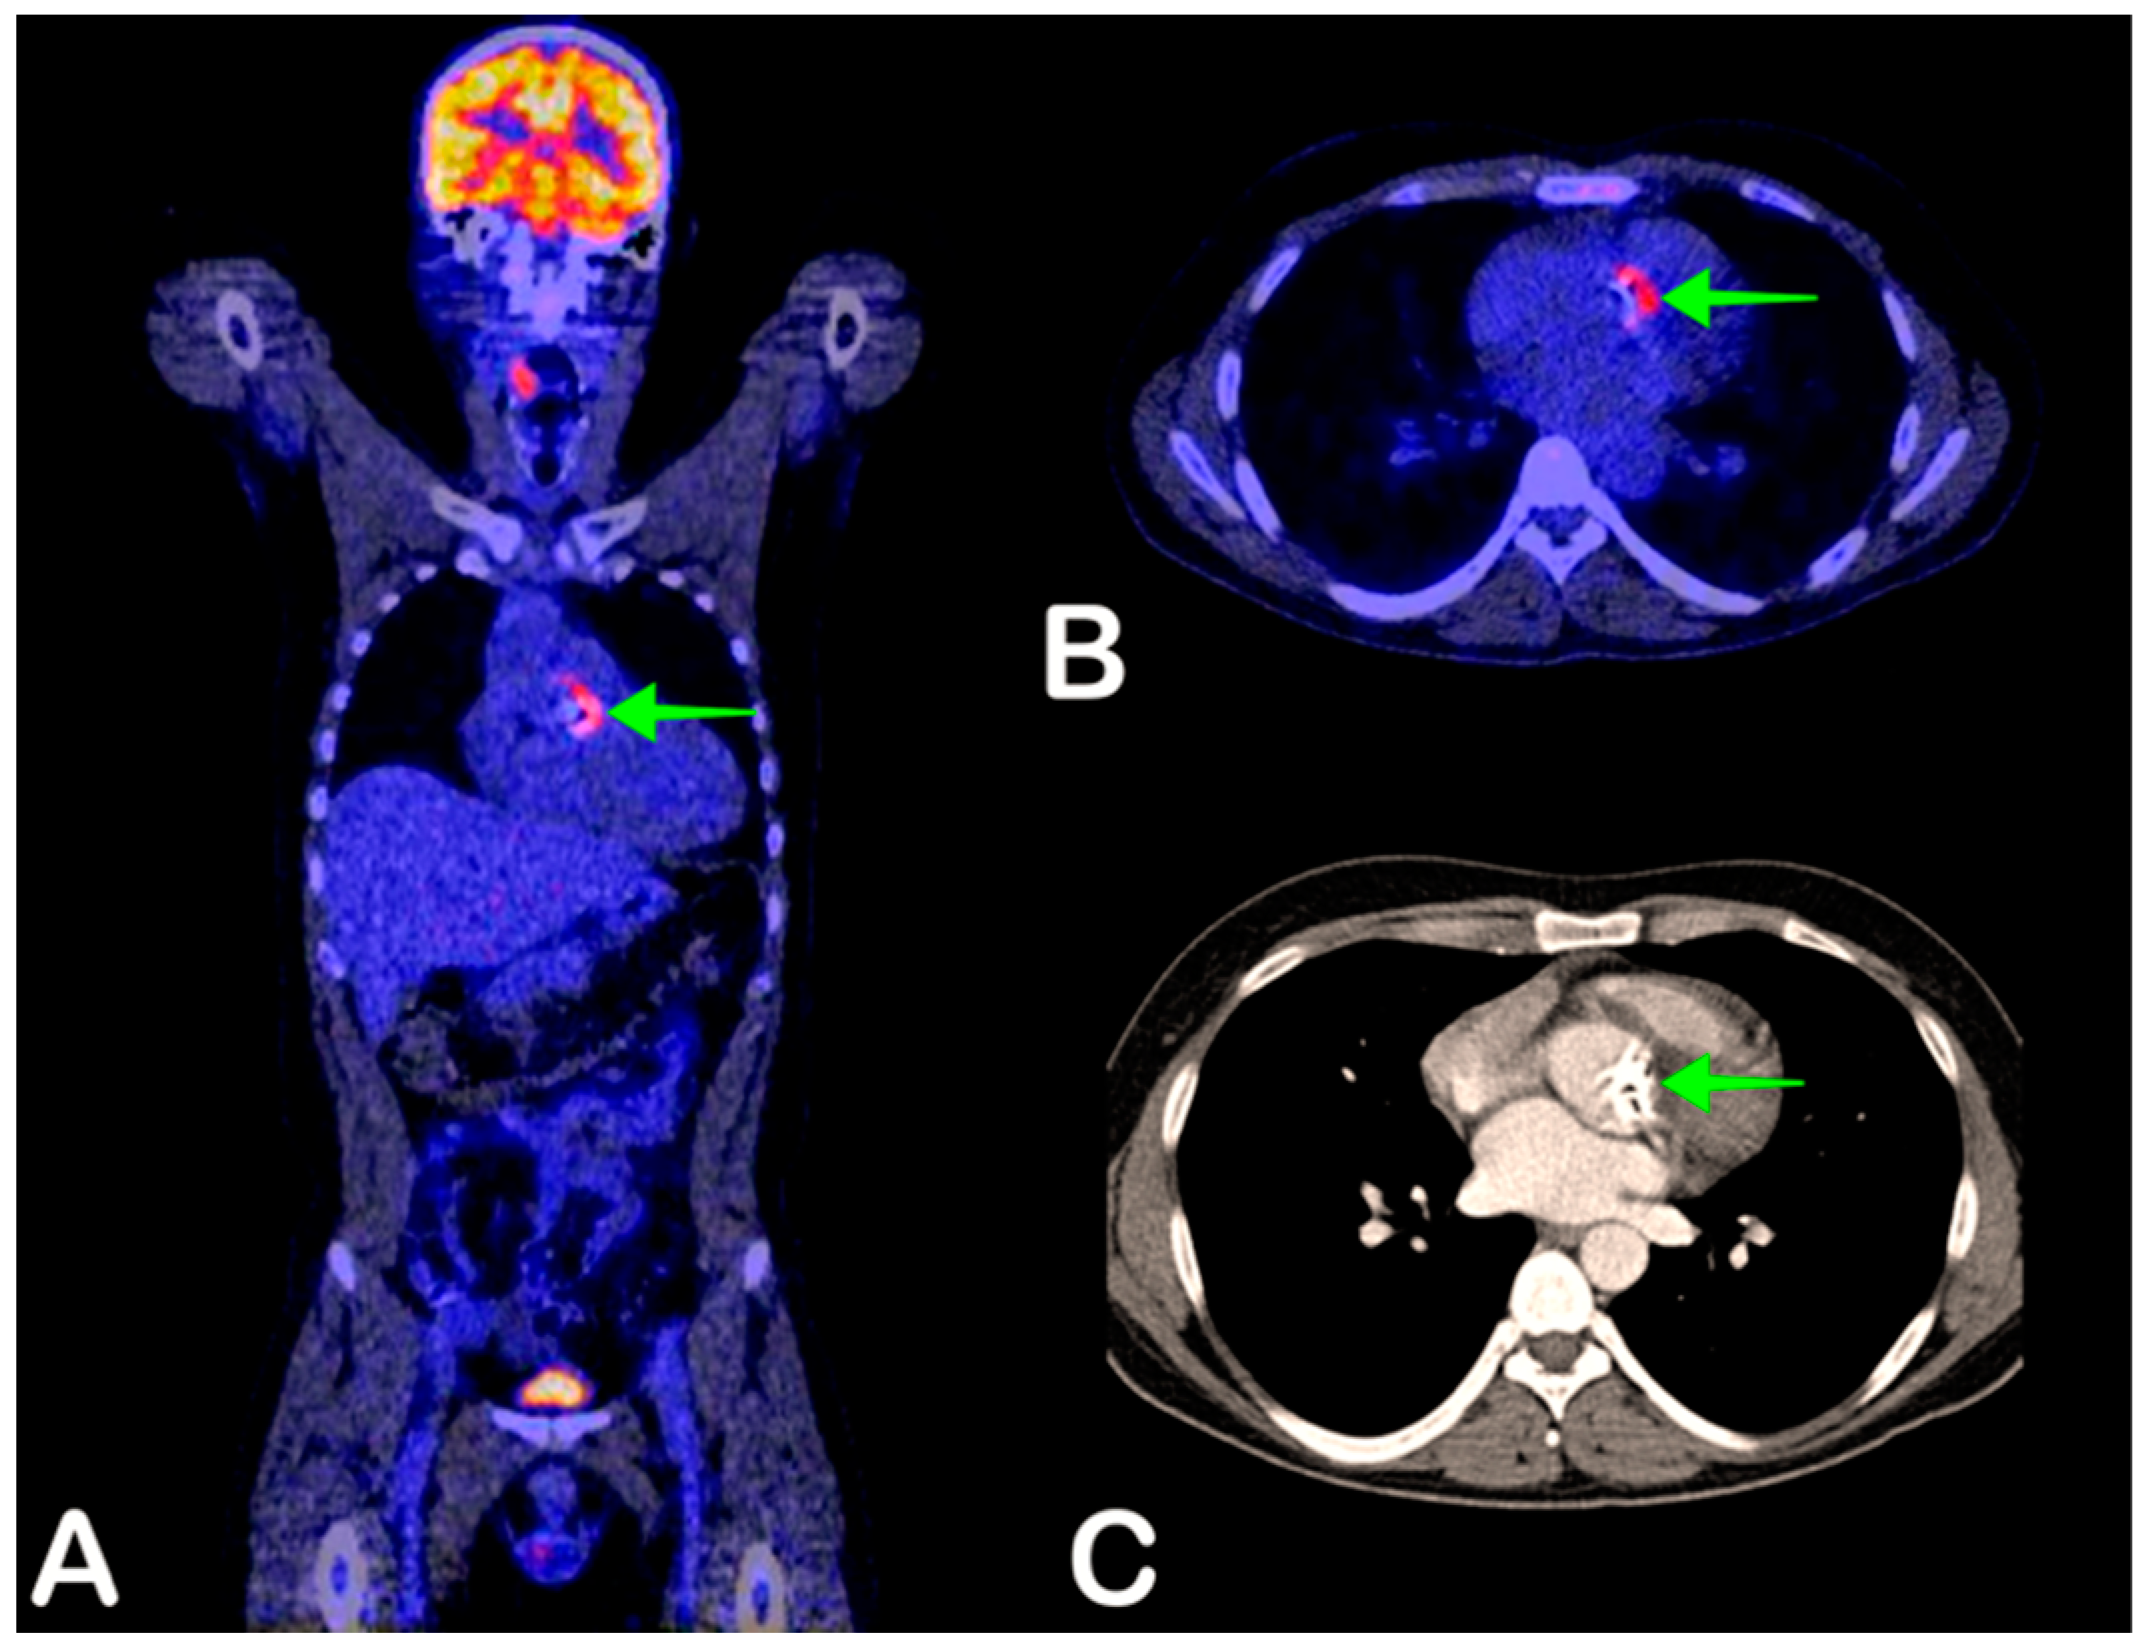

2.3. Infective Endocarditis

- Chen, W.; Dilsizian, V. FDG PET/CT for the diagnosis and management of infective endocarditis: Expert consensus vs evidence-based practice. J. Nucl. Cardiol. 2018, 26, 313–315. [Google Scholar] [CrossRef]

- Gomes, A.; Glaudemans, A.W.J.M.; Touw, D.J.; Van Melle, J.P.; Willems, T.P.; Maass, A.H.; Natour, E.; Prakken, N.H.J.; Borra, R.J.H.; Van Geel, P.P.; et al. Diagnostic value of imaging in infective endocarditis: A systematic review. Lancet Infect. Dis. 2017, 17, e1–e14. [Google Scholar] [CrossRef]

- Habib, G.; Lancellotti, P.; Antunes, M.J.; Bongiorni, M.G.; Casalta, J.-P.; Del Zotti, F.; Dulgheru, R.; El Khoury, G.; Erba, P.A.; Iung, B.; et al. 2015 ESC Guidelines for the management of infective endocarditis. The Task Force for the Management of Infective Endocarditis of the European Society of Cardiology (ESC). Endorsed by: European Association for Cardio-Thoracic Surgery (EACTS), the European Association of Nuclear Medicine (EANM). G. Ital. Cardiol. Rome 2016, 17, 3075–3128. [Google Scholar]

- Erba, P.A.; Pizzi, M.N.; Roque, A.; Salaun, E.; Lancellotti, P.; Tornos, P.; Habib, G. Multimodality Imaging in Infective Endocarditis. Circulation 2019, 140, 1753–1765. [Google Scholar] [CrossRef] [PubMed]